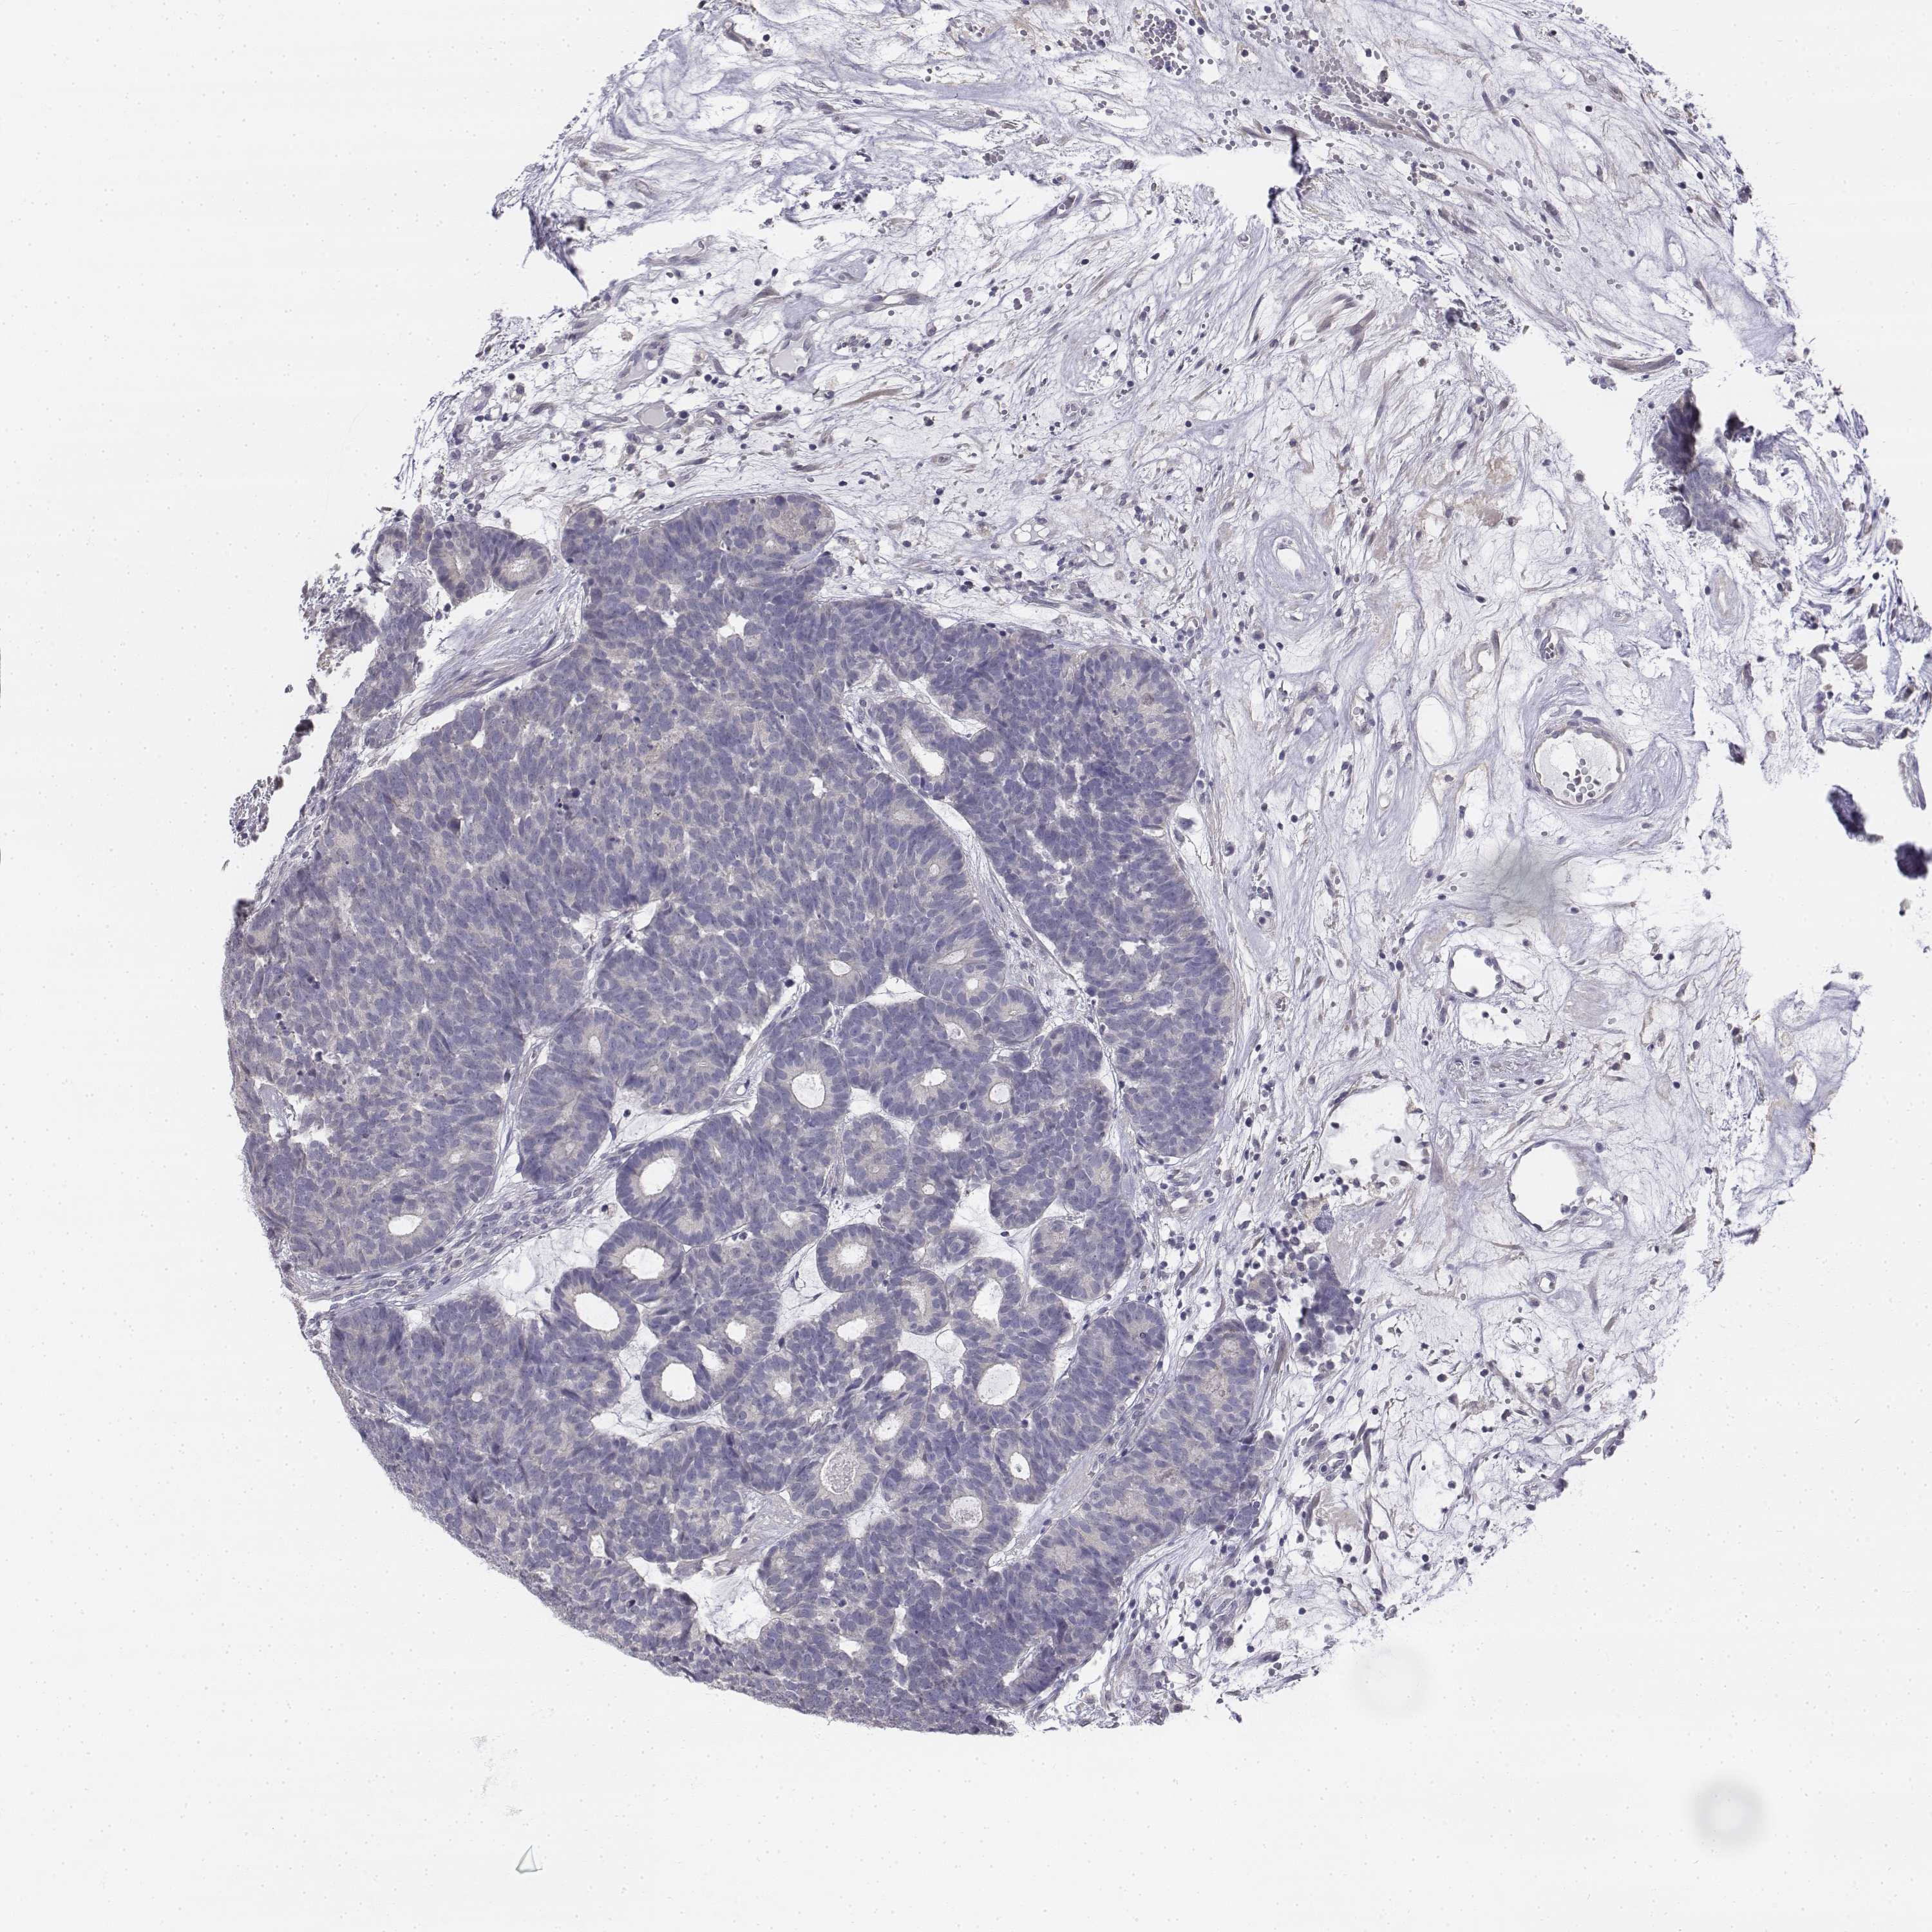

HEAD AND NECK CANCER - Protein expressioni

A mouse-over function shows sample information and annotation data. Click on an image to view it in a full screen mode. Samples can be filtered based on level of antibody staining by selecting one or several of the following categories: high, medium, low and not detected. The assay and annotation is described here.

Antibody stainingi

Antibody staining in the annotated cell types in the current human tissue is reported as not detected, low, medium, or high, based on conventional immunohistochemistry profiling in selected tissues. This score is based on the combination of the staining intensity and fraction of stained cells.

Each image is clickable and will lead to virtual microscopy that enables deeper exploration of all samples and also displays staining intensity scores, fraction scores and subcellular localization as well as patient and tissue information for each sample.

Antibody HPA013138

Antibody CAB016390

Staining

High

Medium

Low

Not detected

Intensity

Strong

Moderate

Weak

Negative

Quantity

>75%

75%-25%

<25%

None

Location

Nuclear

Cytoplasmic/membranous

Cytoplasmic/membranous,nuclear

Squamous cell carcinoma, NOS

Adenocarcinoma, NOS

Squamous cell carcinoma, metastatic, NOS